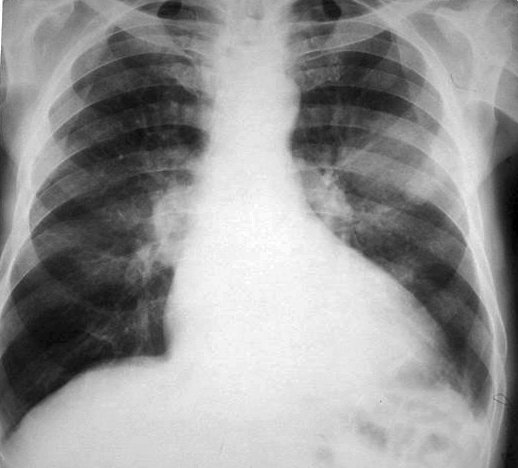

Carcinom bronho-pulmonar periferic

Carcinom periferic mediopulmonar stâng